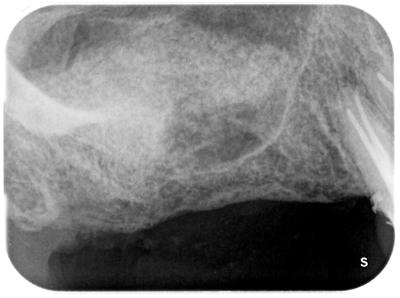

術前

上部から下部に弧状に上顎洞が存在し、インプラント埋入できるような状態ではない。

ラテラル法によるサイナスリフト。

側面から上顎洞内面粘膜(シュナイダー膜)を温存しながら歯槽骨に穴を開け、剥離、できた空間に骨移植行う方法。